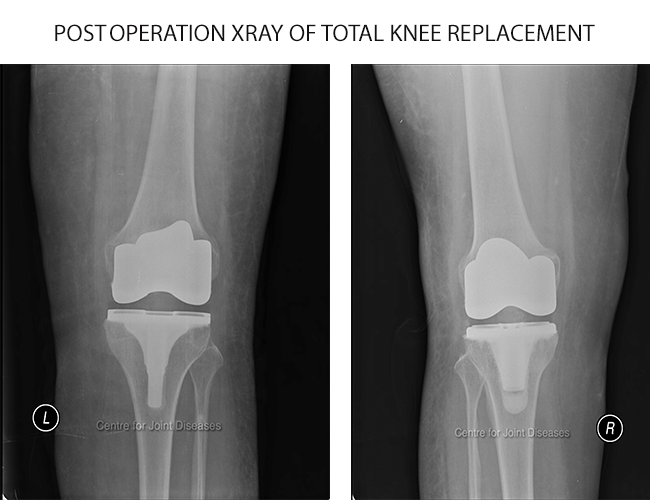

Knee joint is exposed using a midline incision on the front of knee. Joint is exposed after separating the muscle and cutting through the capsule. The worn and damaged surface of bone and cartilage from lower end of femur (thigh bone) and upper end of tibia (shin bone) are removed and shaped to accept the prosthetic metal implants. A plastic spacer is again inserted between these two components. The soft tissues around the knee are carefully balanced to correct the alignment of the joint and optimize the function of knee